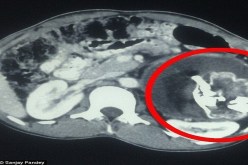

أفغانستان.. استخراج جنين من بطن رضيع استقبل مستشفى كابول طفلا يعاني من انتفاخ في البطن. واشتبه الأطباء أولا بإصابته بورم "ويلمز" (ورم كلوي). يظهر أحيانا لدى… 02 أفريل